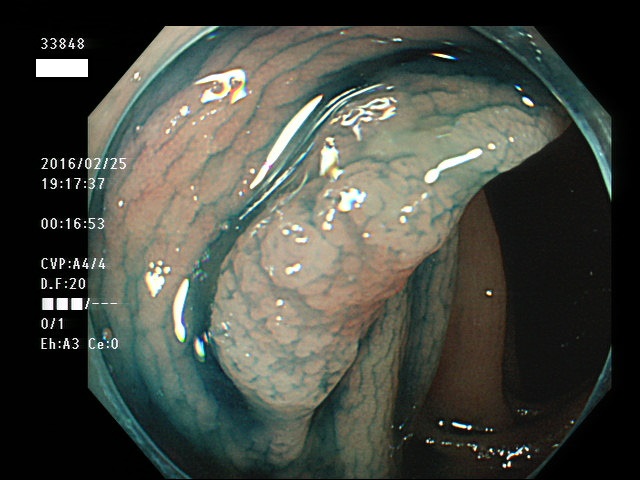

上記100名より抽出した平坦・陥凹型腺腫(=癌化の危険が高いが見落としやすい病変)の内視鏡写真